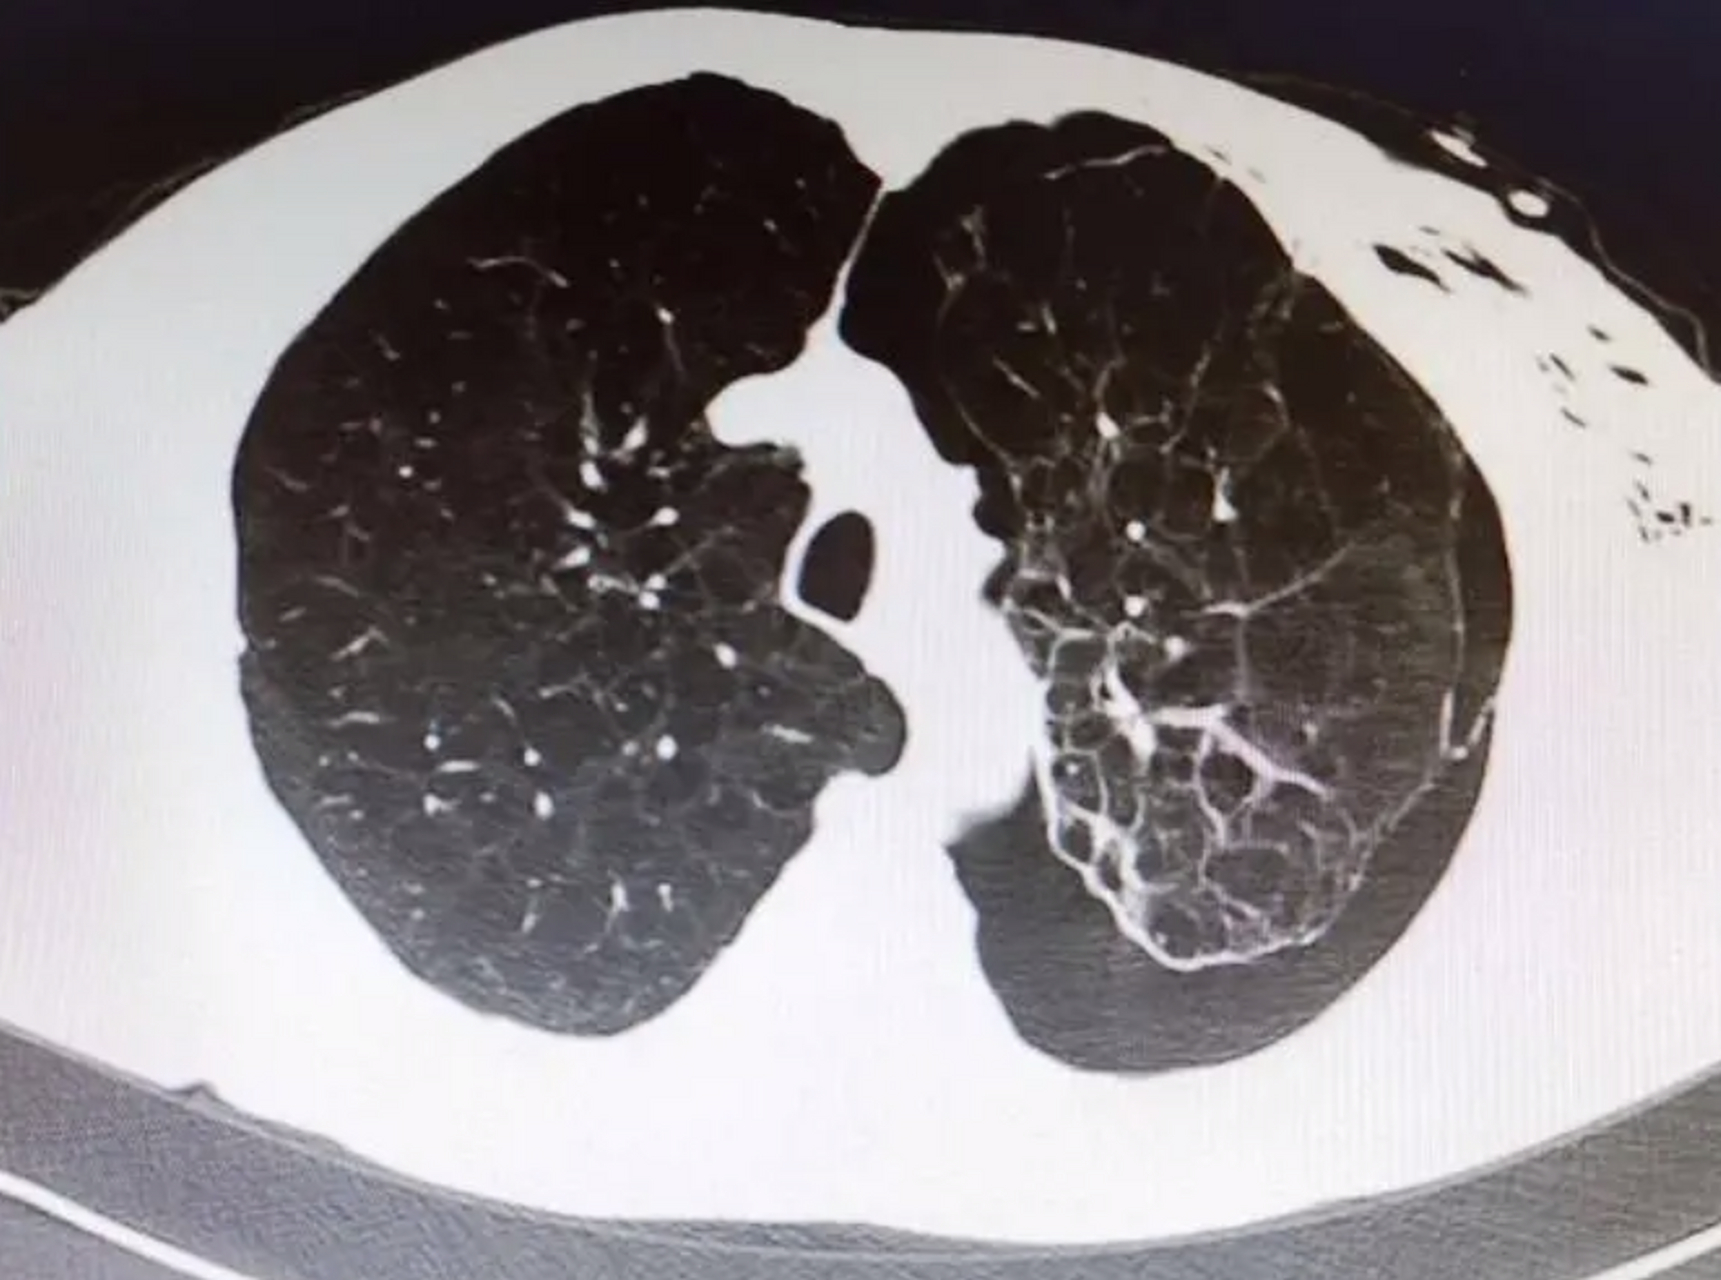

双侧多发肺大泡一例